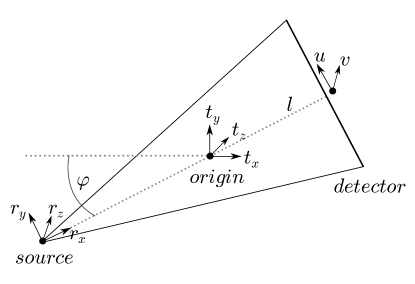

With reference to Figure 2, each scatter projection image with coordinates is updated based on a rigid translation of an object at the centre of rotation by onto a FDK reconstruction of the measurements. We define a new set of coordinates , due to rotation of the source around by the angle by

We note that due to the projection, a translation along leads to a change in scaling, and translations in lead to shifting. If we define the distances as the lengths from source to origin and the detector respectively, the transformation to adjust the projection is